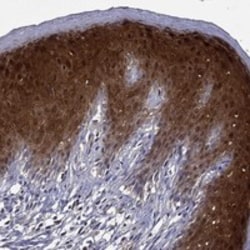

Invitrogen™ GLTP Polyclonal Antibody

| Applications | Immunohistochemistry (Paraffin), Western Blot |